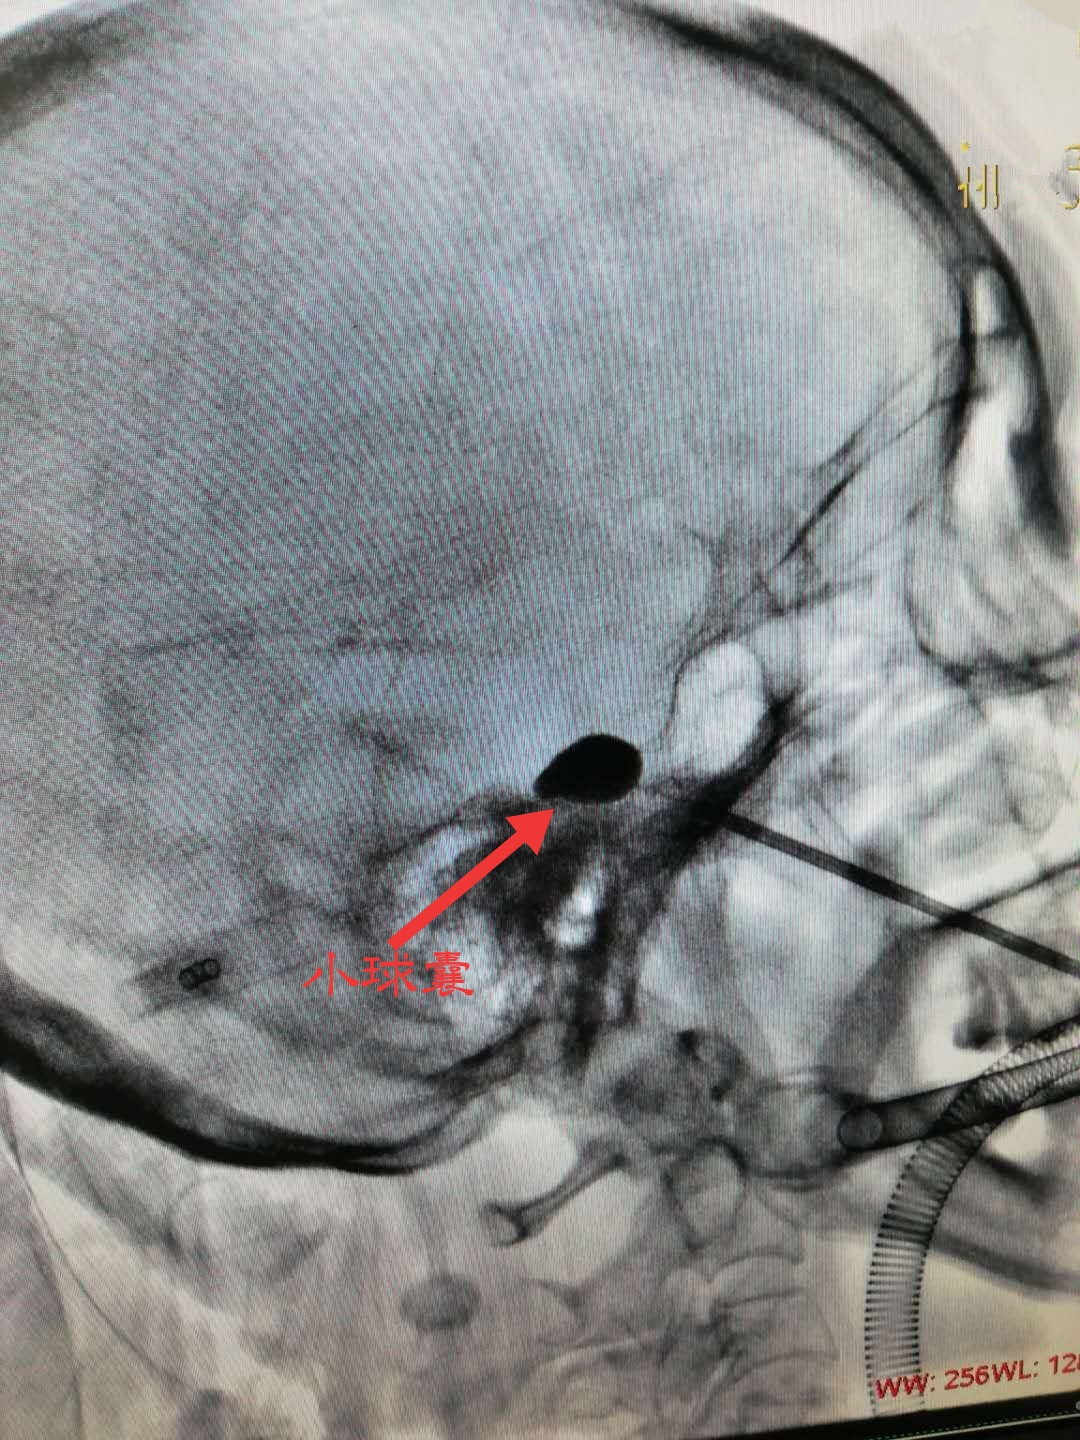

疼痛科团队通过与张阿姨沟通并经家属的同意之后,决定避免开颅风险,采用“微球囊压迫术”进行治疗。张阿姨的微球囊压迫术历时不到30分钟,术后不仅疼痛感消失,吃饭、喝水、刷牙也不受影响。

微球囊压迫术是近年来治疗三叉神经痛的新手段,手术时患者全程无痛,平均手术时长为10~30分钟,避免了开颅手术可能存在的致残、致死等严重后果。(疼痛科 龙婷)